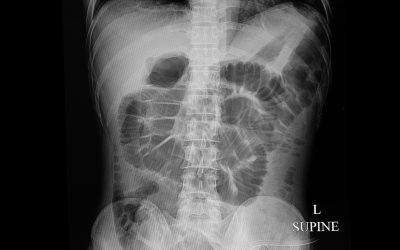

Što je ileus

Ileus predstavlja prekid probavne peristaltike, funkcije crijeva koje stišći i odvode fekalije i otpadne tvari iz organizma. Često ga se naziva paralitički ileus a uzrokovan je mehaničkim preprekama k